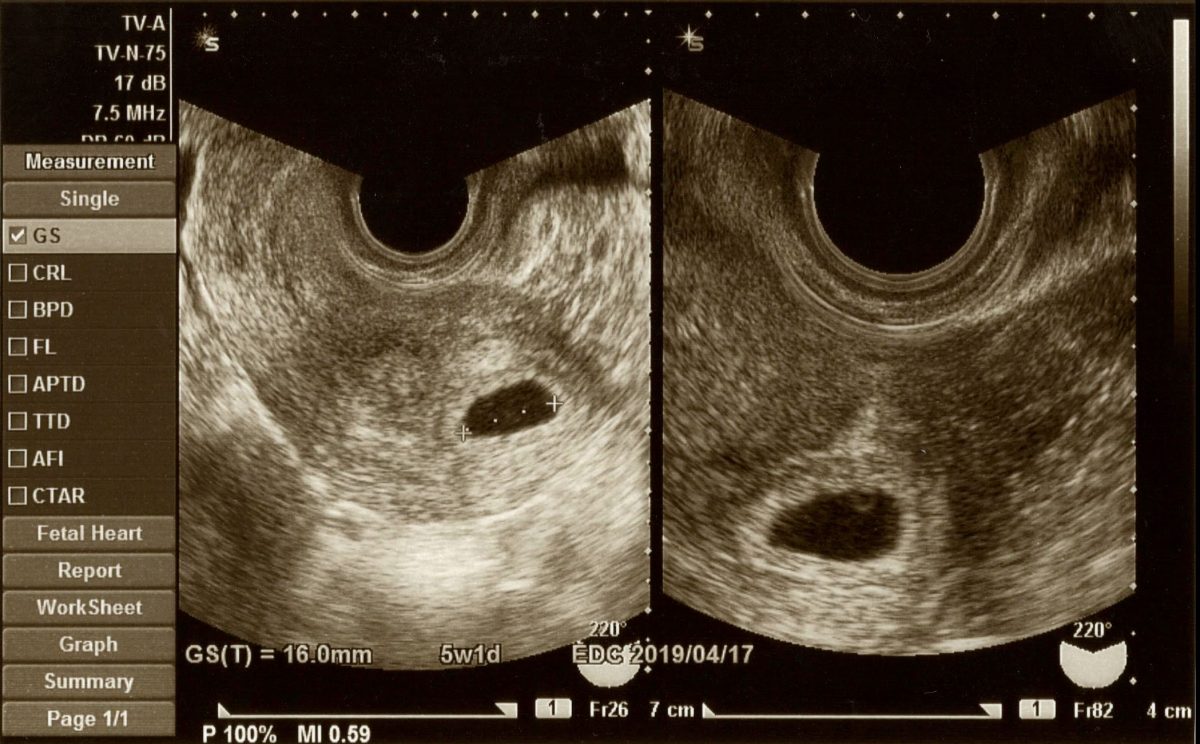

卵巣嚢腫の発生を防ぐ方法はなく、ほとんどの場合、内診中に発見されます。嚢胞に応じて、医師は妊娠検査、骨盤超音波検査、腹腔鏡検査などの検査を指示する場合があります。この場合、麻酔が必要であり、処置中に嚢胞が除去されます。そしてCA 125と呼ばれる血液検査。